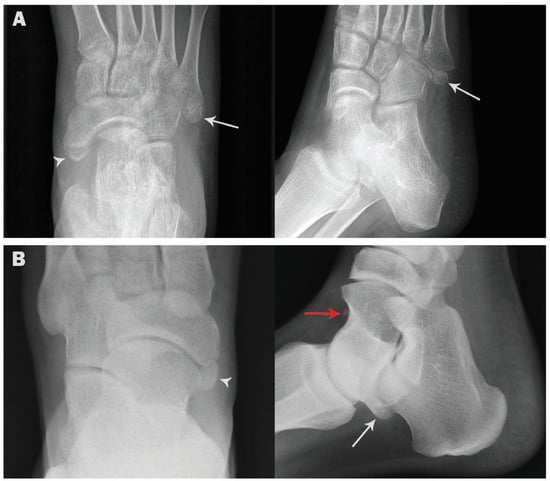

| Os vesalianum | 11 (1.1) | 7 (1.4) | 4 (0.8) | 9 (1.3) | 2 (0.6) |

| p value | 0.5466 ns | 0.5187 ns | |||

| Os subfibulare | 6 (0.6) | 2 (0.4) | 4 (0.8) | 3 (0.4) | 3 (0.9) |

| p value | 0.6866 ns | 0.3979 ns | |||

| Os supranaviculare | 7 (0.7) | 6 (1.2) | 1 (0.2) | 4 (0.6) | 3 (0.9) |

| p value | 0.1237 ns | 0.6886 ns | |||

| Os infranaviculare | 3 (0.3) | 2 (0.4) | 1 (0.2) | 2 (0.3) | 1 (0.3) |

| p value | 1.000 ns | 1.000 ns | |||

| Os subtibiale | 1 (0.1) | 1 (0.2) | 0 (0) | 0 (0) | 1 (0.3) |

| p value | 1.000 ns | 0.3260 ns | |||